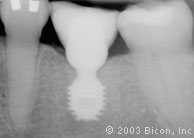

1. | 用一颗4.5mm x 6.0mm、一颗5.0mm x 6.0mm和一颗6.0mm x 5.7mm短种植体和三个一体化基台冠修复一颗左下颌第二前磨牙、第一磨牙和第二磨牙。 |